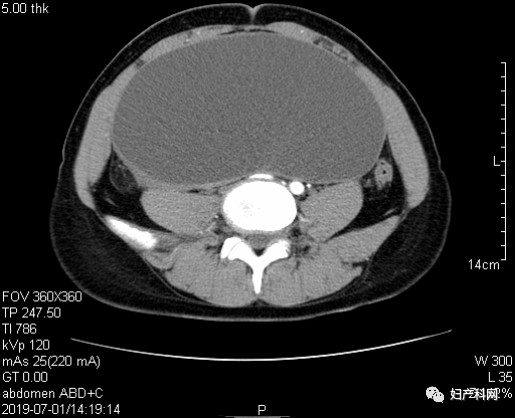

2019-07-01本院全腹部CT平扫+增强示:子宫后倾,正常大小,轮廓清楚,宫腔显示规则。子宫上方见一类椭圆形囊性块,大小约19.1x10.2x23cm,囊液较粘稠,CT值约16Hu,囊壁稍厚尚光整,未见明显分隔,囊壁上未见明显乳头,增强扫描囊壁强化。右侧卵巢可及,正常大小。盆腔淋巴结未见肿大,盆底少许腹水。中上腹扫描示:肝、脾、肾、胰等脏器未见明显占位灶或异常密度影,胆囊无殊,大网膜、肠系膜、壁腹膜未见明显结节灶,腹主动脉旁淋巴结无肿大。诊断结果:1、子宫上方囊性包块,考虑左卵巢良性病变,囊腺瘤可能;内异囊肿待排;2、中上腹扫描未见明显异常。